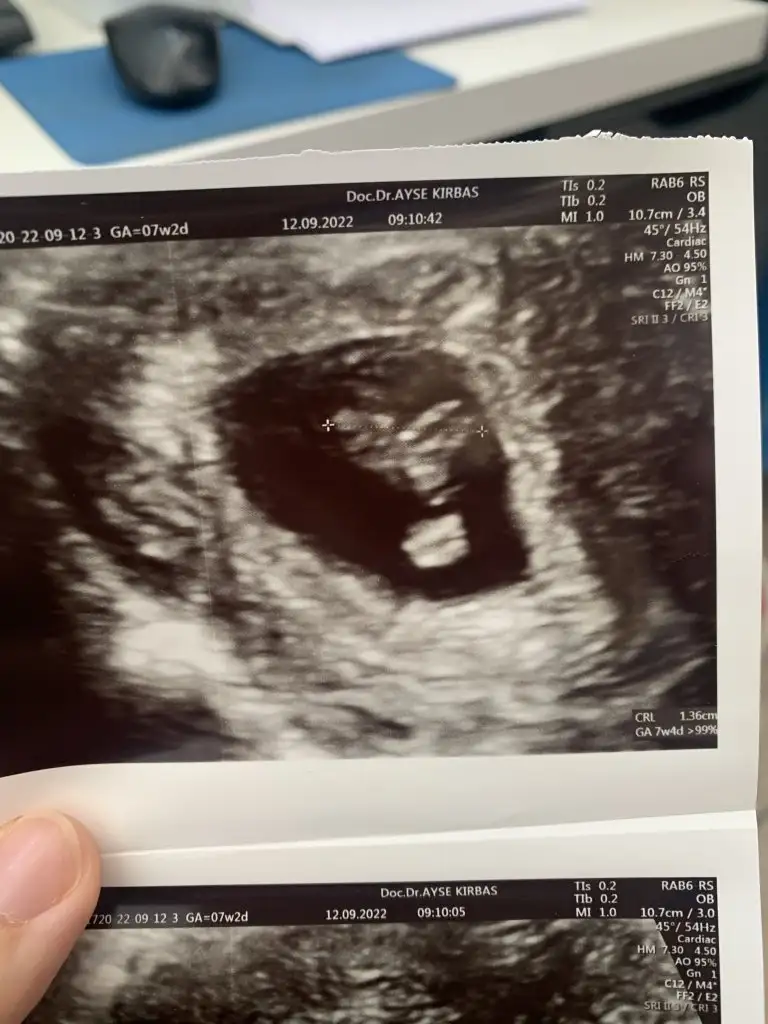

Vajinal ultrason 7+3 şimdiden teşekkürler:)